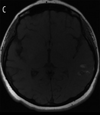

Brain MRI

T1 Weighted Imaging

- Ideal for brain parenchyma

- With the addition of contrast, this can differentiate causes of inflammation

- Fluid is hypointense (similar to CT imaging)

- Methemoglobin, fat, and protein are hyperintense